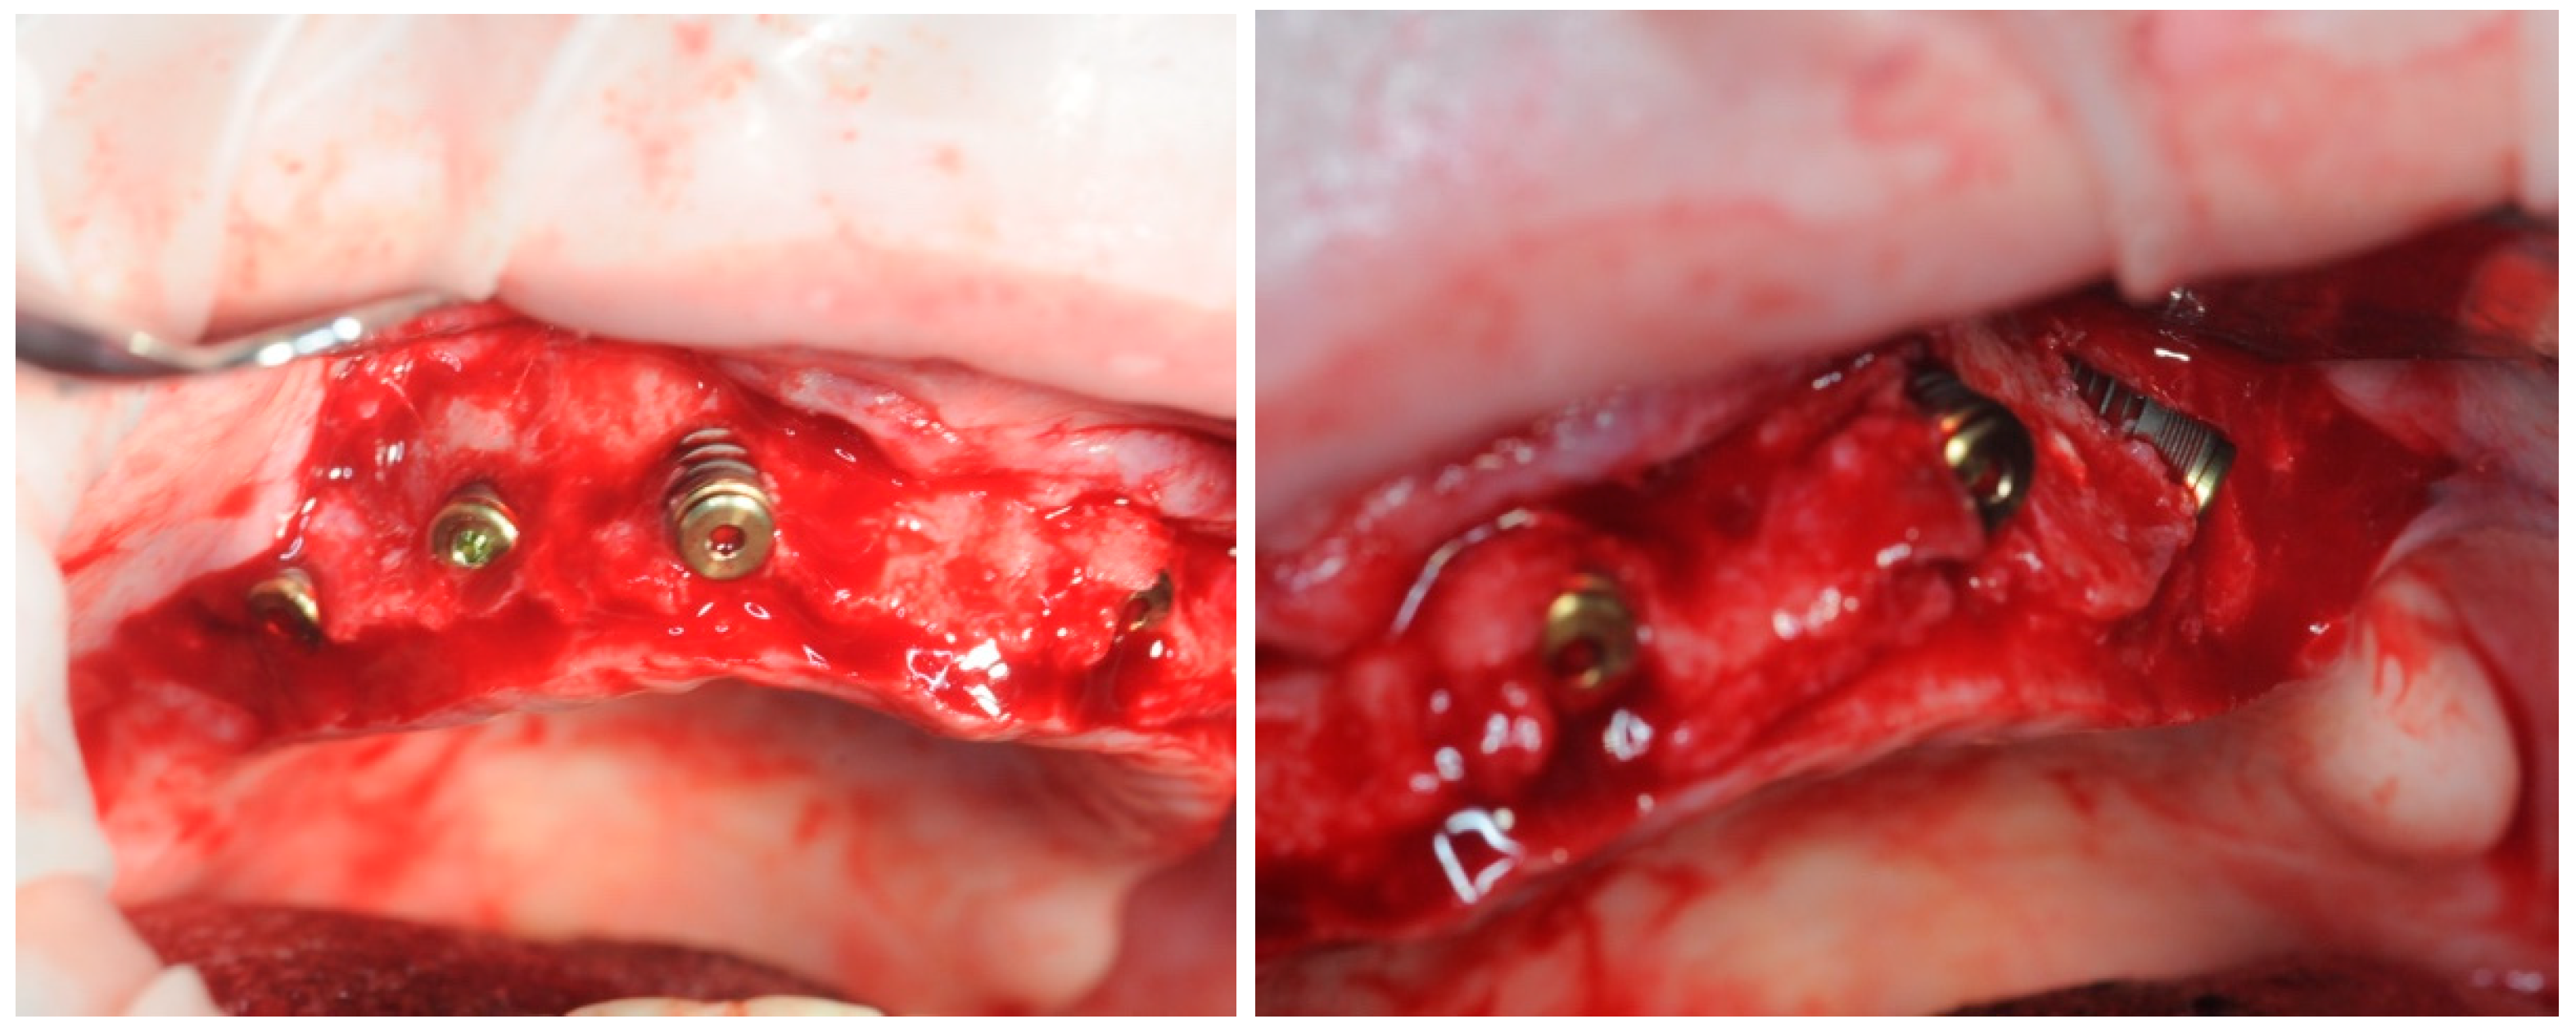

2.3. Re-Entry Surgery

3.3. Hard Tissues Gain